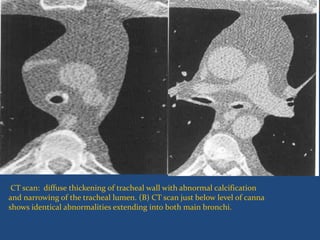

CT scan: diffuse thickening of tracheal wall with abnormal calcification

and narrowing of the tracheal lumen. (B) CT scan just below level of canna

shows identical abnormalities extending into both main bronchi.